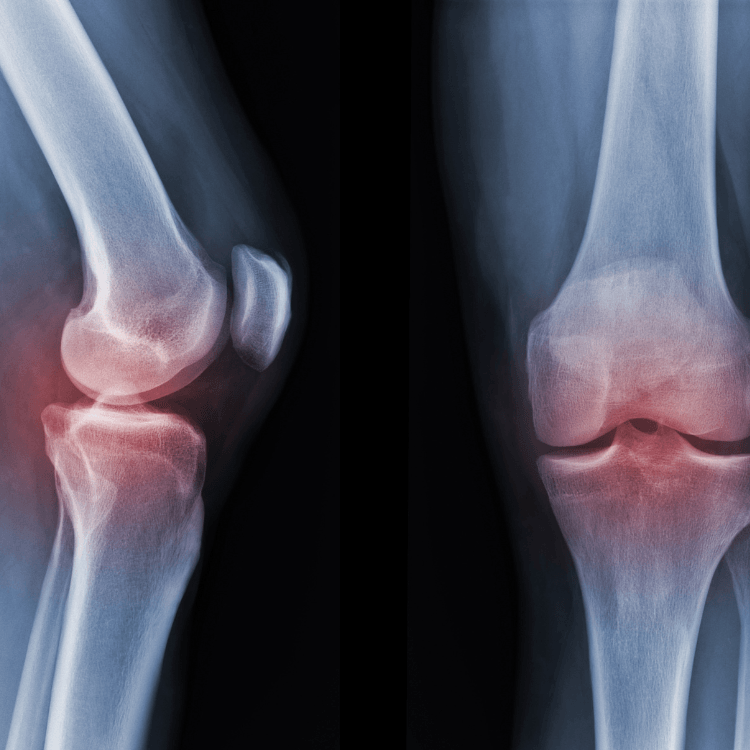

Knee osteoarthritis (OA) can be a frustrating and debilitating condition, impacting everything from daily activities to overall quality of life. Fortunately, there are multiple strategies available that we utilize at Pain Free to help manage symptoms and improve function. Let’s explore the key treatment options available for knee OA, focusing on exercise, education, and additional support.